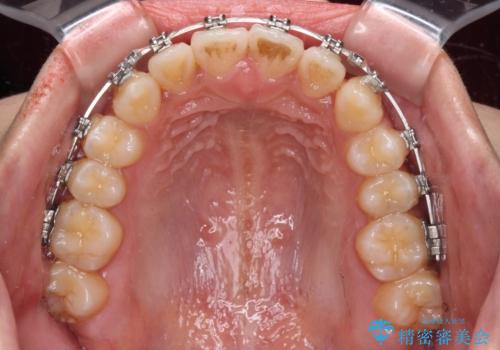

- メタルブラケット

上顎歯列が狭窄していたため、急速拡大装置により上顎骨を側方に拡大し、その後ワイヤー装置にて矯正治療を行うこととしました。

舌の突出癖が開咬の原因であったので、改善のための舌トレーニングを行っていただきました。

舌トレーニングは後戻りにも大きく影響するため、とても重要なトレーニングです。